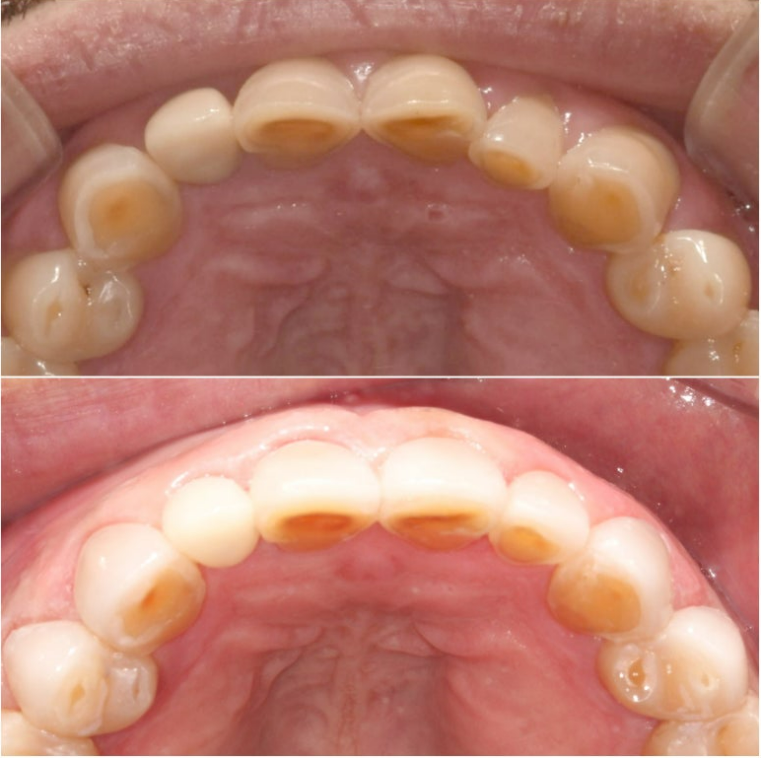

치아가 오랜 세월 마모로 인하여 짧아진 상태이며, 파란 화살표는 크라운 입니다.

배열이 가지런하면 말만 무삭제가 아니라 100% 무삭제가 가능합니다.

사실 배열이 가지런하지 않더라도 100% 무삭제 라미네이트는 가능합니다.

파란 화살표 치아가 뒤로 들어가 있으니 배열을 맞추기 위해서 두껍게 제작이 될 것 입니다.

장기적으로 치아와 잇몸건강을 해치게 되는 거죠

무삭제 라미네이트의 실제 두께를 알 수 있는 사진입니다.

삭제를 하지 않았음에도 원래 치아보다 두꺼워짐이 거의 없죠

무삭제 라미네이트의 핵심은 바로 얇게 만드는 것 입니다.